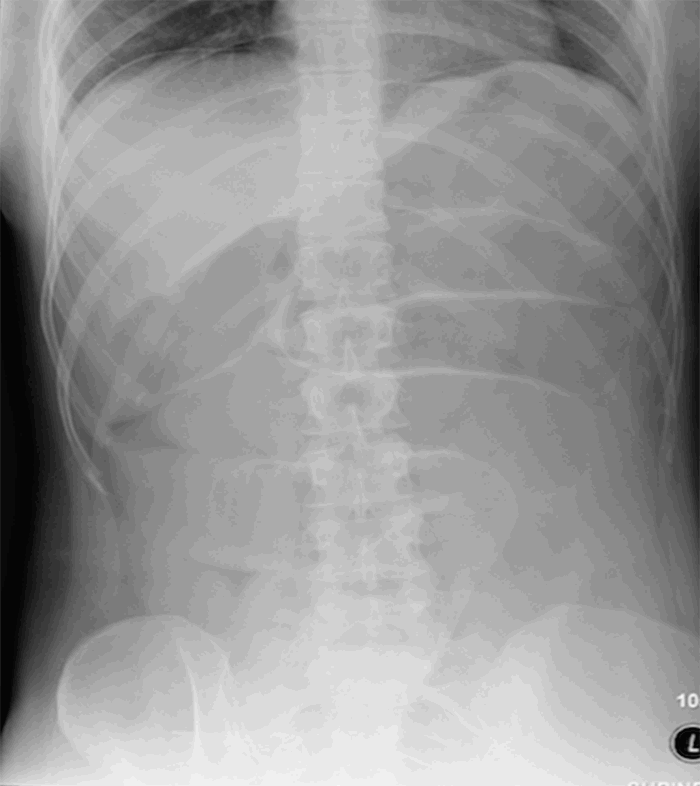

The following day, the patient experienced three episodes of diarrhea, and by the evening, she developed altered mental status, abdominal distension, and tachycardia. Stat labs demonstrated marked hemoconcentration with hematocrit 56.9 percent, white blood cell count 16 K/mcL, lactate 10.2 mmol/L, and bicarbonate 10 mmol/L, for which the patient received aggressive fluid resuscitation. Further diagnostic workup included pan-cultures and C. difficile toxin assay. Empiric antibiotic therapy was initiated along with transfer to a higher level of care. An abdominal X ray showed marked small bowel dilation (Figure 1). A nasogastric tube was placed and immediately productive of two liters of bilious fluid. The patient was taken emergently for exploratory laparotomy. Shortly after induction, she became pulseless and required 45 seconds of chest compressions and intravenous epinephrine. Fortunately, her pulse returned, and the procedure revealed no evidence of obstruction, peritonitis, bowel ischemia, or anastomotic leak.

Figure 1. Abdominal X ray revealing dilated loops of the small bowel